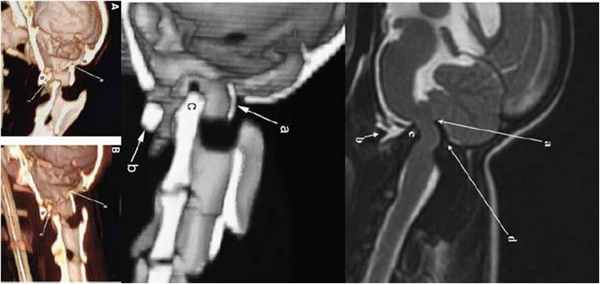

Применение нативного кт позволяет получить надежные доказательства (является методом выбора) наличия атланто-аксиальной нестабильности и оверлеппинга однако следует помнить, что последний может быть динамическим и меняться при определенных положениях головы.

Построение мультипланарных реконструкций на КТ особенно помогает при оценке типа повреждения и используется для получения дополнительных данных для хирургического лечения, а именно пространственных соотношений позвоночного канала, степень зрелости скелета, объем боковых масс атланта, объем и степень атрофии костей черепа. И поэтому по нашему убеждению – является ОБЯЗАТЕЛЬНЫМ! Они как и трехмерные реконструкции поверхностей полезны для планирования хирургических операций на позвоночнике.

На мрт исследовании нашего пациента – здесь представлена сагитальная Т2 взвешенная последовательность, определяется смещение аксиального позвонка в дорсальном направлении по отношению к атланту, дислокация дорсальной дужки атланта к задней черепной ямке с тяжелой компрессией как мозжечка, так и спинного мозга.

Мрт пациента с краниоцервикальной мальформацией (Впадина Дьюи, сирингомиелия в шейном отделе)